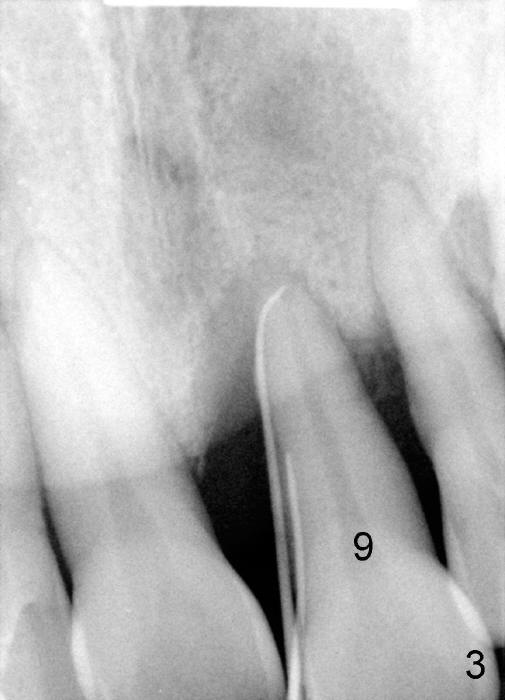

A 52-year-old man has severe periodontal disease (Fig.1-3). It appears that the upper teeth are non salvageable and are best treated by hybrid denture. But his finance is strained.

The provisional of #9 is still wiggling a little bit buccolingually. It is probably due to loose connection between the implant and the abutment, although follow up PAs do not support it (Fig.7,8; ^: bone graft at the time of immediate implants).